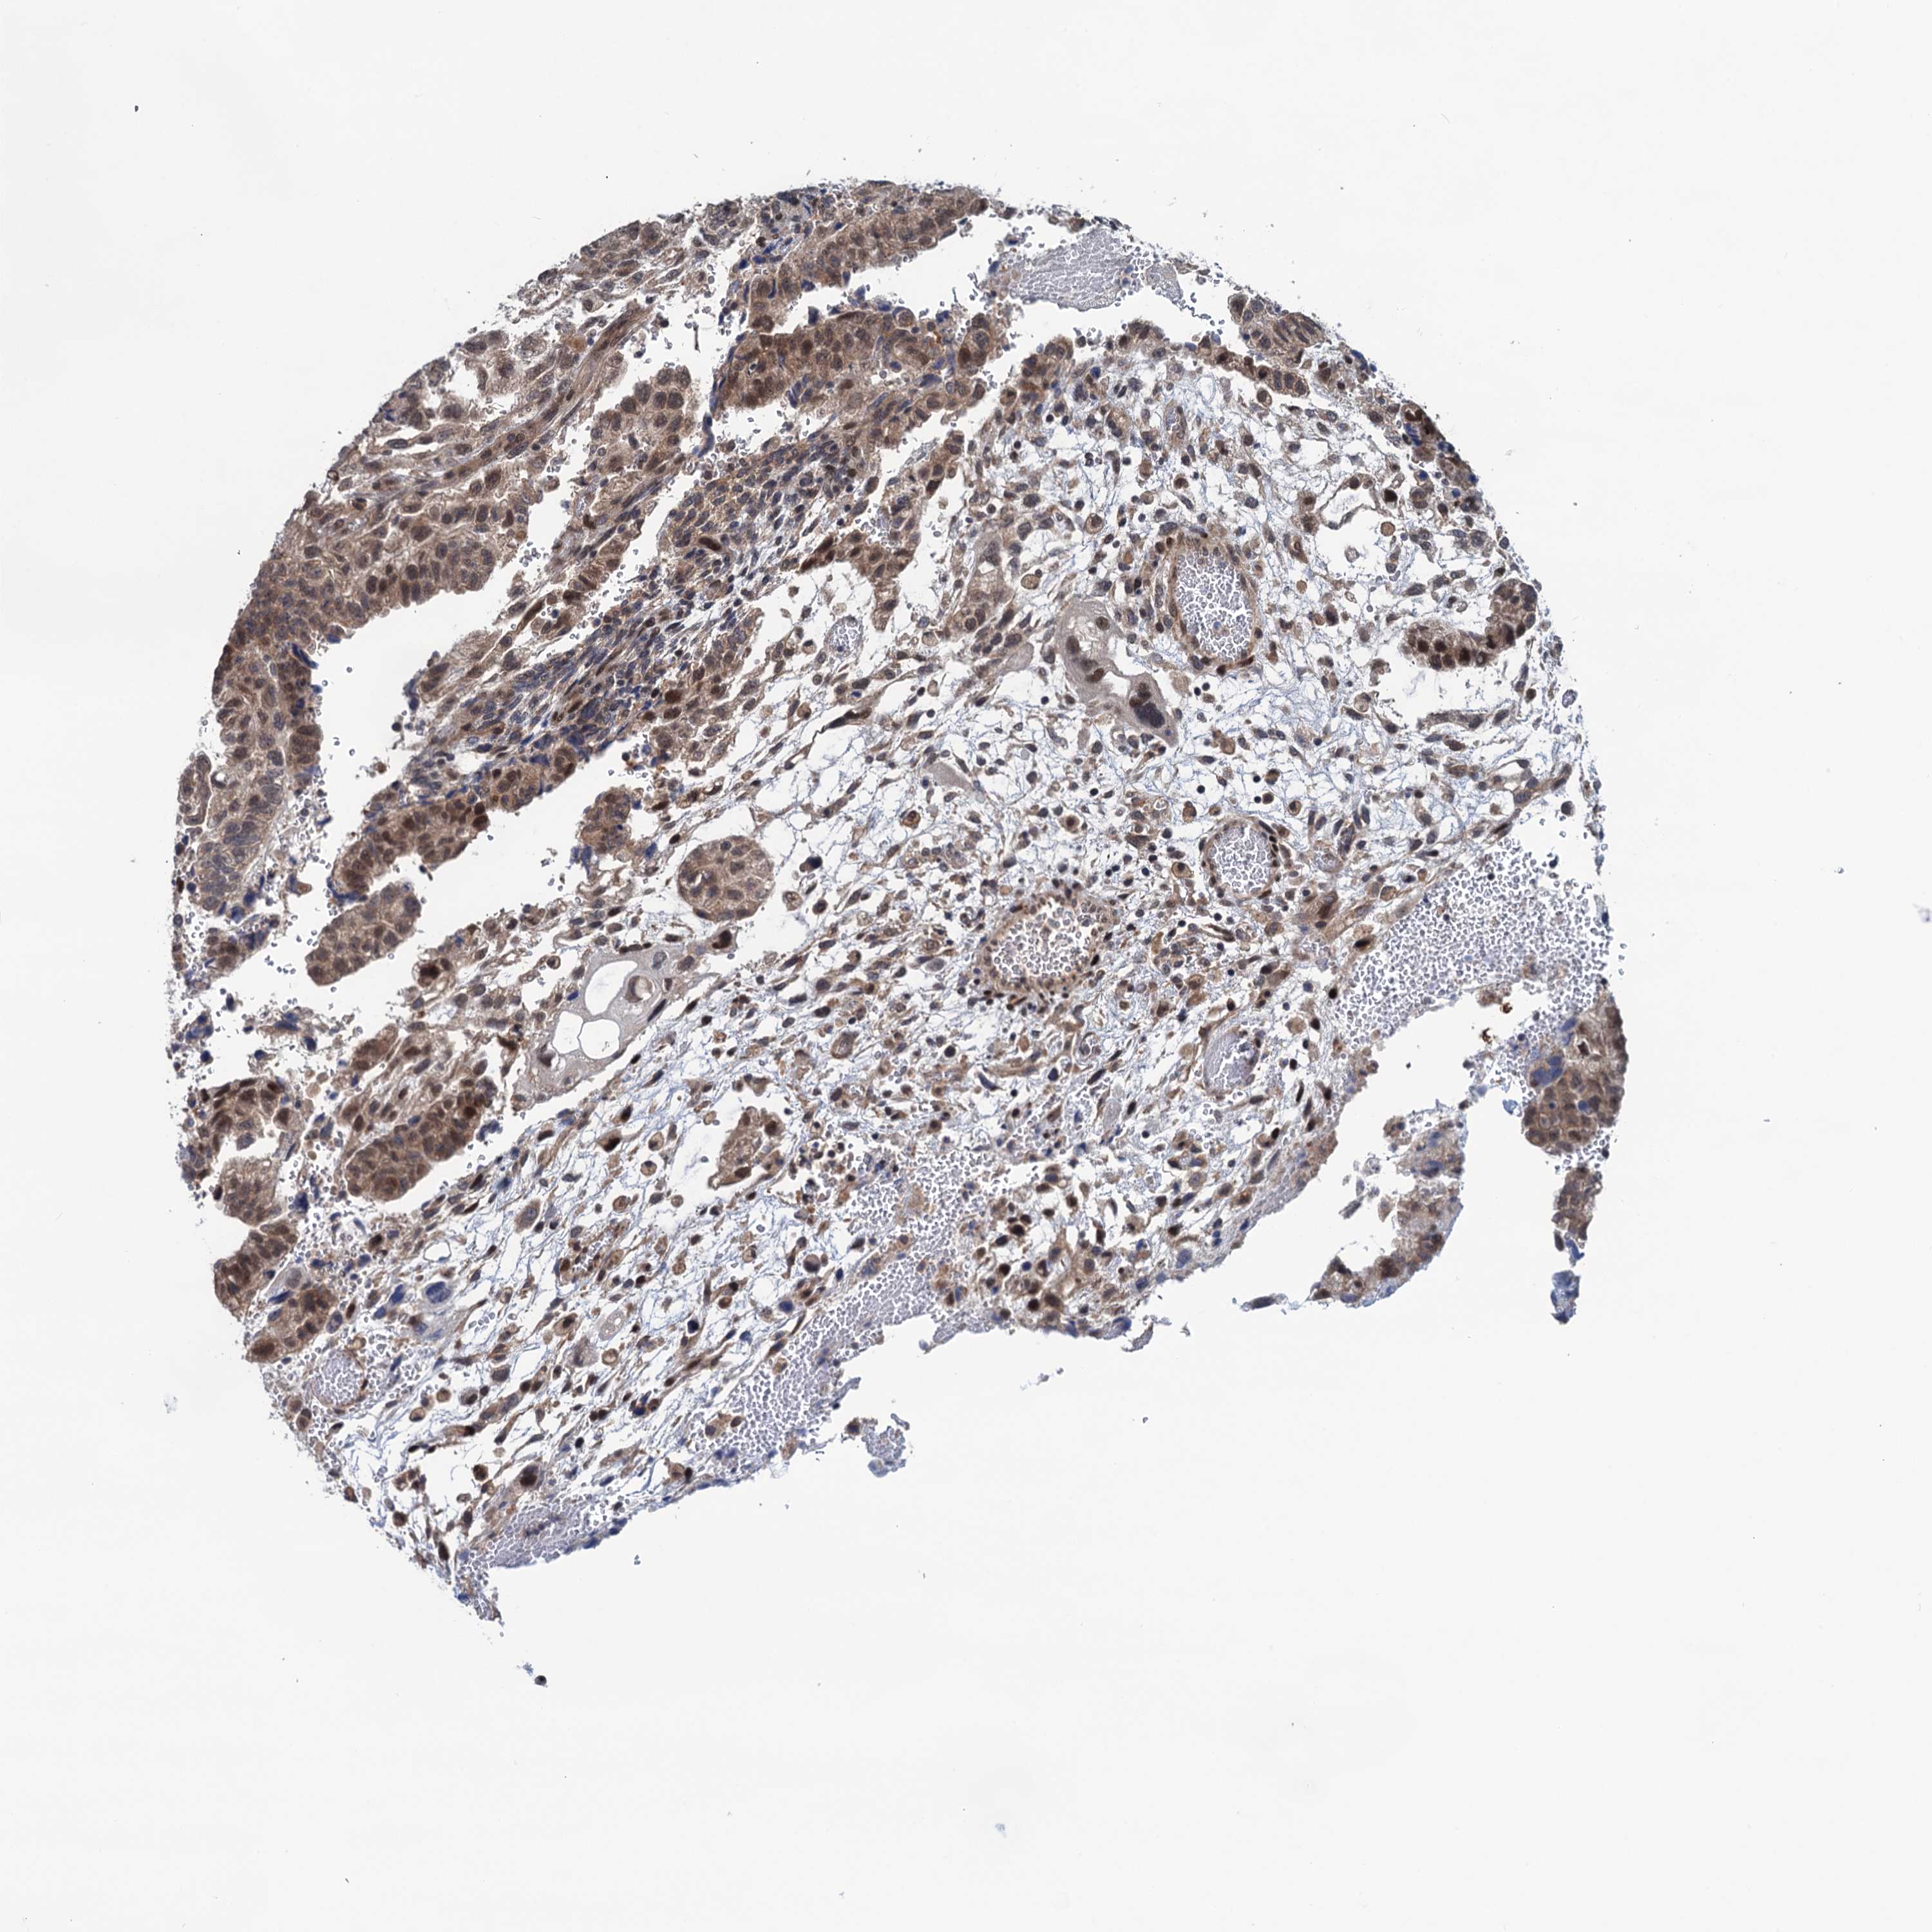

TESTIS CANCER - Protein expressioni

A mouse-over function shows sample information and annotation data. Click on an image to view it in a full screen mode. Samples can be filtered based on level of antibody staining by selecting one or several of the following categories: high, medium, low and not detected. The assay and annotation is described here.

Note that samples used for immunohistochemistry by the Human Protein Atlas do not correspond to samples in the TCGA dataset.

Antibody stainingi

Antibody staining in the annotated cell types in the current human tissue is reported as not detected, low, medium, or high, based on conventional immunohistochemistry profiling in selected tissues. This score is based on the combination of the staining intensity and fraction of stained cells.

Each image is clickable and will lead to virtual microscopy that enables deeper exploration of all samples and also displays staining intensity scores, fraction scores and subcellular localization as well as patient and tissue information for each sample.

Antibody HPA041906

Staining

High

Medium

Low

Not detected

Intensity

Strong

Moderate

Weak

Negative

Quantity

>75%

75%-25%

<25%

None

Location

Nuclear

Cytoplasmic/membranous

Cytoplasmic/membranous,nuclear

Carcinoma, Embryonal, NOS

Seminoma, NOS